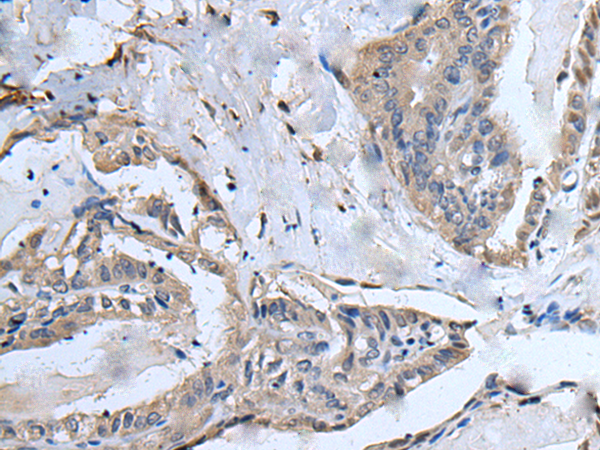

ELISA, IHC |

IHC positive control: |

Human esophagus cancer and human breast cancer |

IHC Recommend dilution: |

25-100 |